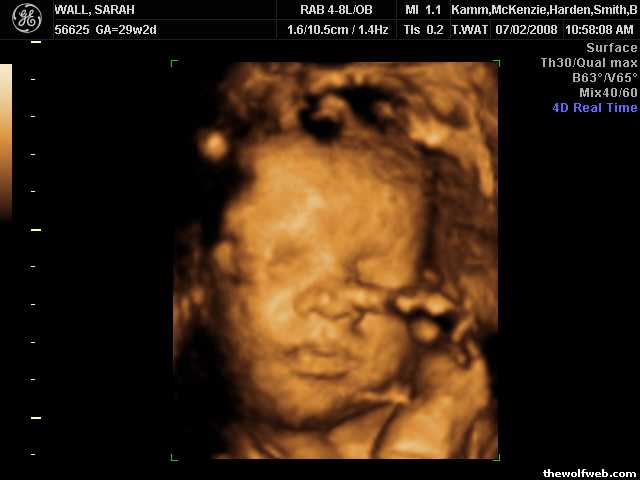

Yeah she's so black that's why her skin is white in a 4D ultrasound of an unborn baby at 29 week gestation that wasn't even fully developed at the time. You know nothing you ignorant redneck fuck...Now I remember why I stopped posting here.

Those 4D ultrasounds are awesome. I got one of my daughter and it's amazing how well facial features show up. I had an appointment to get one more, but my daughter decided to come several weeks early.

Yeah they are pretty neat. I can tell in the ultrasound pictures that she's going to look just like me...so I'm super excited about that.